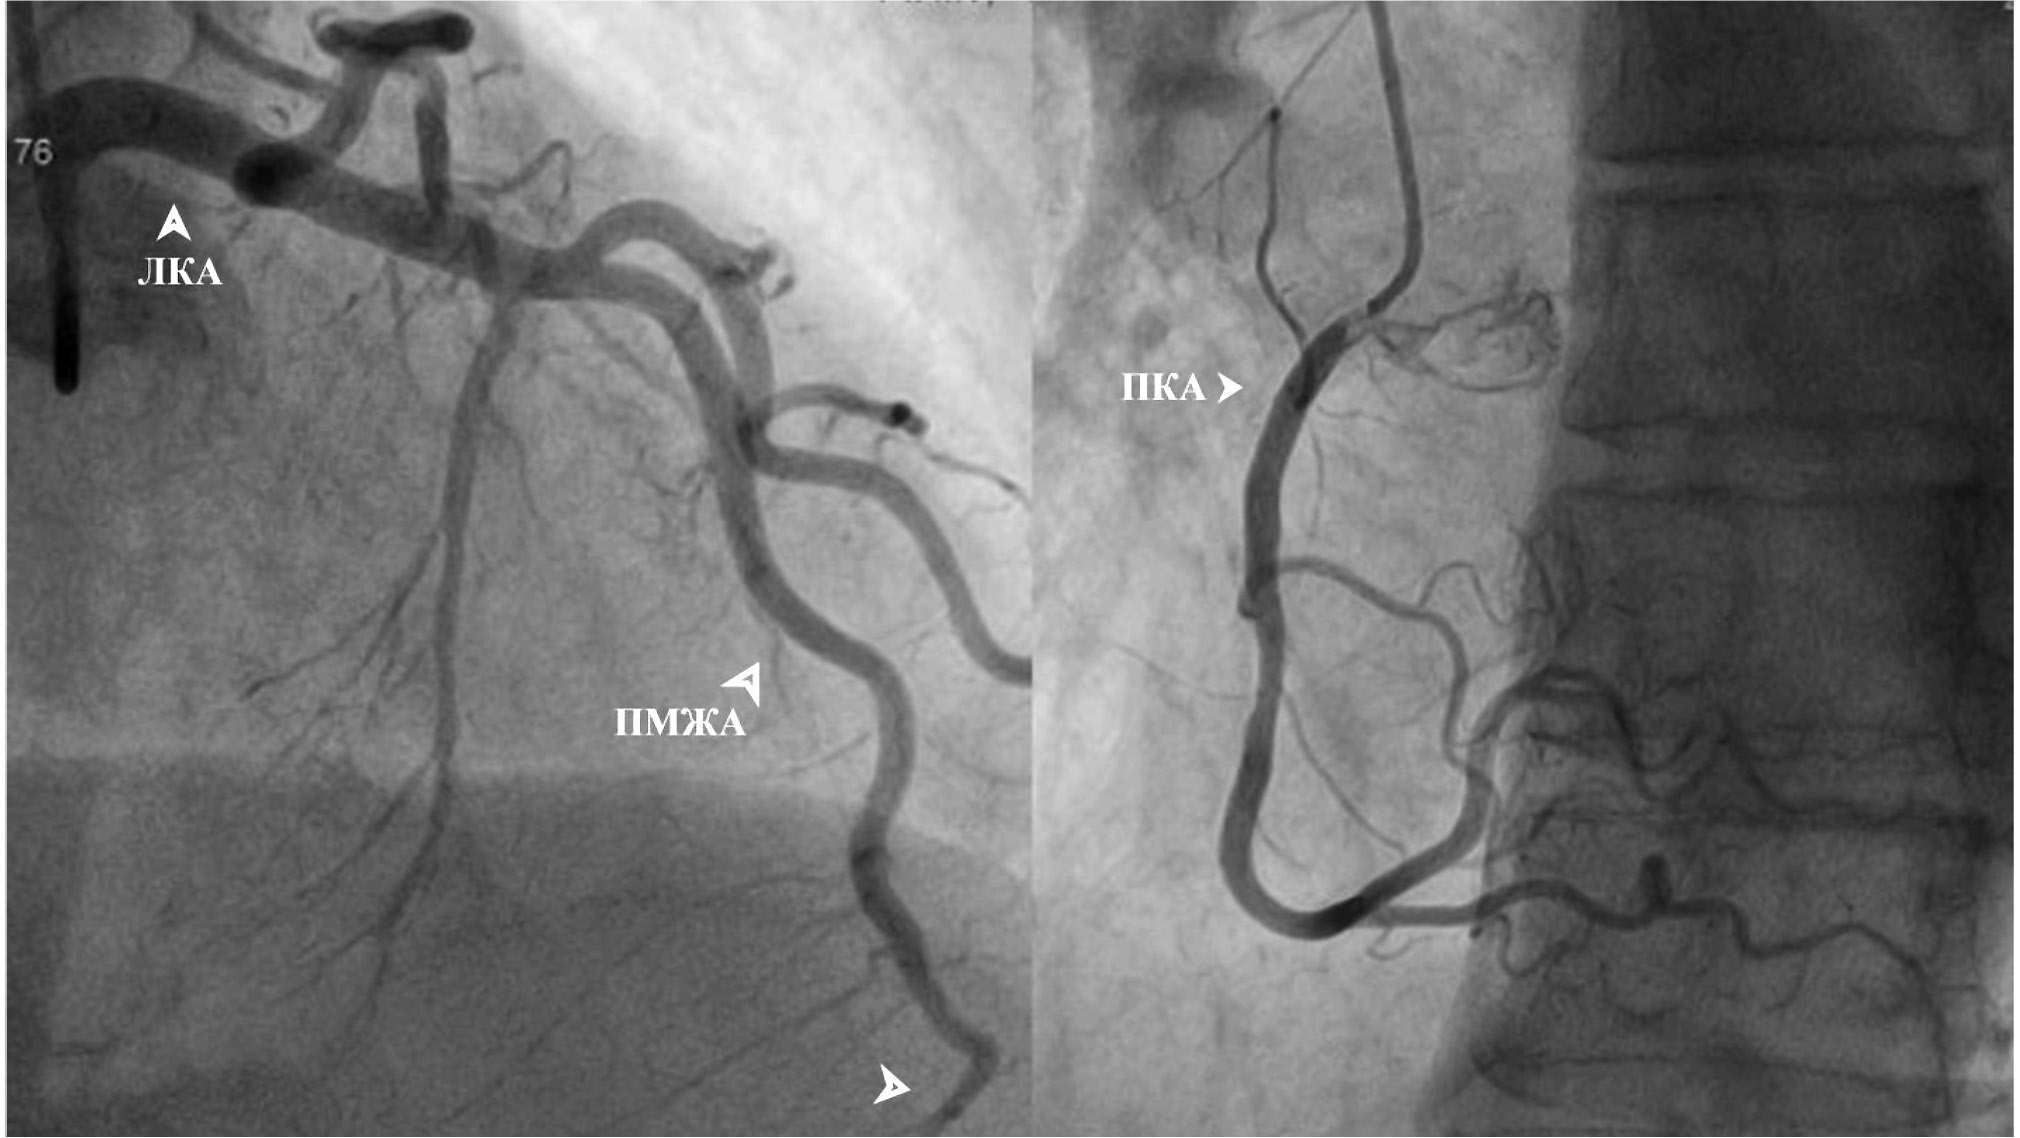

По данным КАГ (рис. 2) в передней межжелудочковой артерии был выявлен мышечный мост в дистальной трети, стенозирующий артерию в диастолу до субокклюзии, остальные артерии без значимых изменений.

Рис. 2. Результат коронарографии. Стрелка слева внизу указывает на место мышечного мостика.

Примечание. ЛКА — левая коронарная артерия, ПМЖА — передняя межжелудочковая артерия, ПКА — правая коронарная артерия.

Fig. 2. Coronary angiography result. The arrow at the bottom left indicates the place of the muscular bridge.

Note. ЛКА — left coronary artery, ПМЖА — anterior interventricular artery, ПКА — right coronary artery.